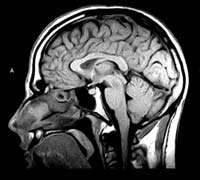

L'imagerie

par résonnance magnétique (IRM) L’avènement

de l’IRM à la fin des années 1970 a eu l’effet d’une

bombe dans le milieu médical. Cette nouvelle technique n’utilisait

ni les rayon X, ni les ultrasons, mais faisait plutôt appel aux champs magnétiques

en exploitant des propriétés physiques de la matière au niveau

sub-atomique, en particulier de l’eau qui constitue environ les trois quart

de la masse du corps humain. L’IRM, en plus d’une définition

supérieure au CT scan, permet aussi d’obtenir non seulement des coupes

axiales du cerveau comme le CT scan, mais aussi des coupes sagittales et coronales.

Bien que l’utilisation du CT scan soit encore prédominante pour

la poitrine et l’abdomen, l’IRM est l’outil de prédilection

pour le cerveau, les extrémités des membres et la colonne vertébrale.